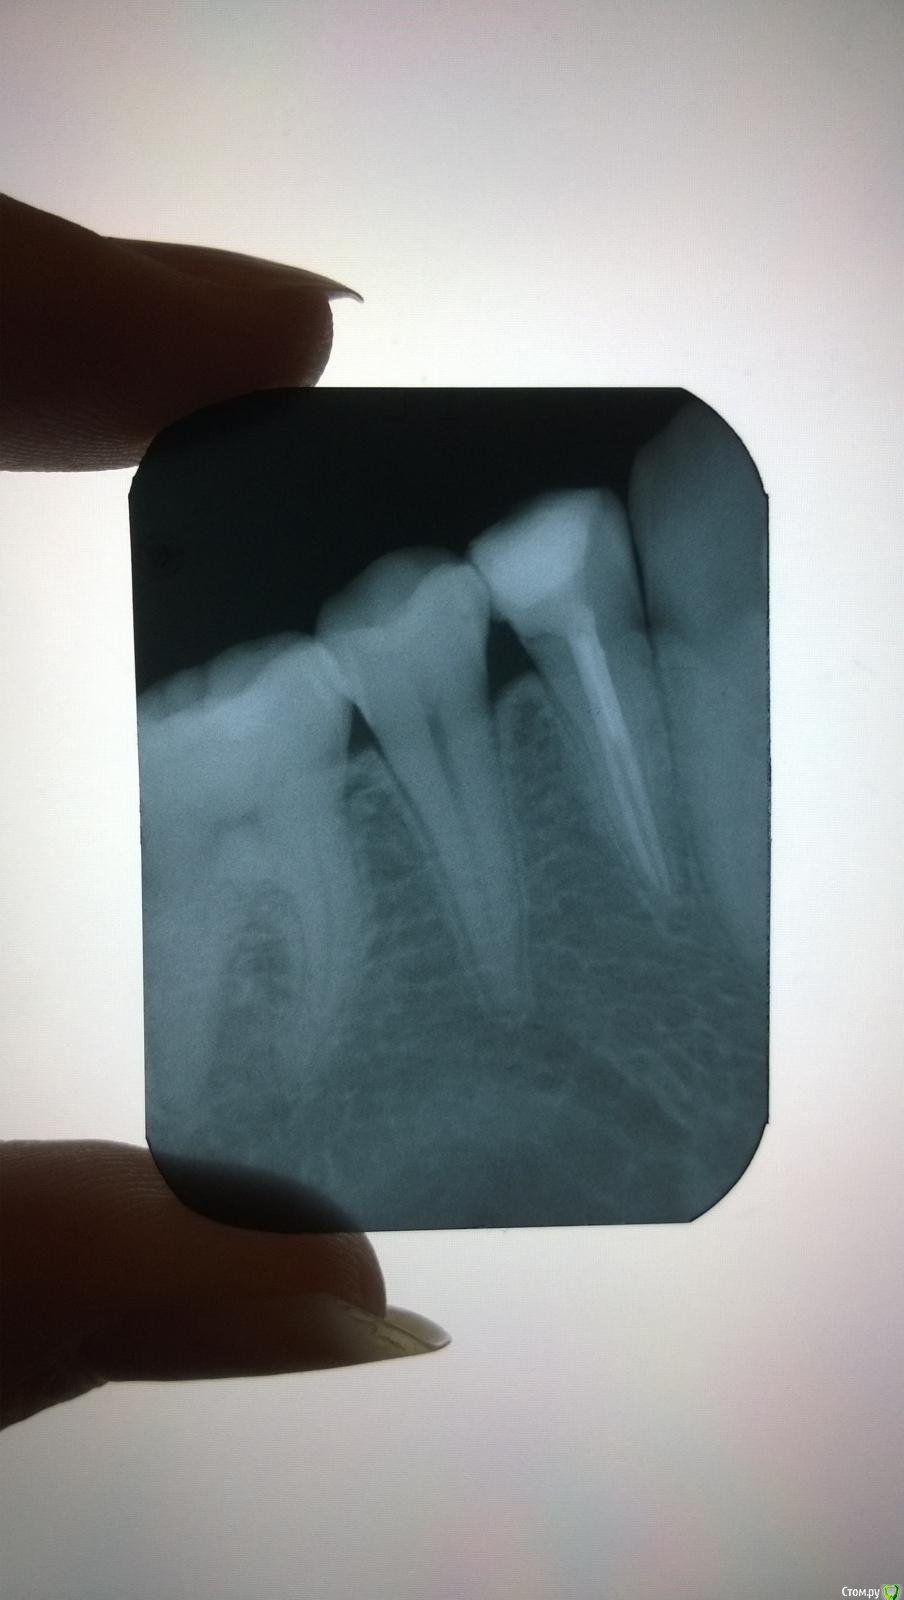

naomi Опубликовано 5 октября, 2015 Поделиться Опубликовано 5 октября, 2015 Здравствуйте!Так сложились обстоятельства, что разболевшийся зуб пришлось лечить у нового для меня врача. Как мне сказали, зуб надо помещать под коронку.Поскольку сама в стоматологии ничего не понимаю, очень хотелось бы узнать, качественно ли было проведено лечение каналов, поскольку не хотелось бы ставить коронку на нехорошо вылеченный зуб. Заранее благодарю всех откликнувшихся на мою проблему:-) Ссылка на комментарий

Гарриевич Опубликовано 5 октября, 2015 Поделиться Опубликовано 5 октября, 2015 По снимку все хорошо 1 Ссылка на комментарий

St. Опубликовано 6 октября, 2015 Поделиться Опубликовано 6 октября, 2015 Все ок. Коронку действительно надо. 1 Ссылка на комментарий